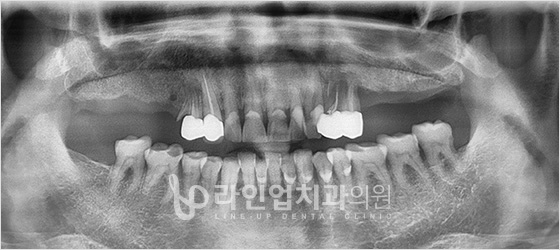

Before

After

Дээд арааны имплант